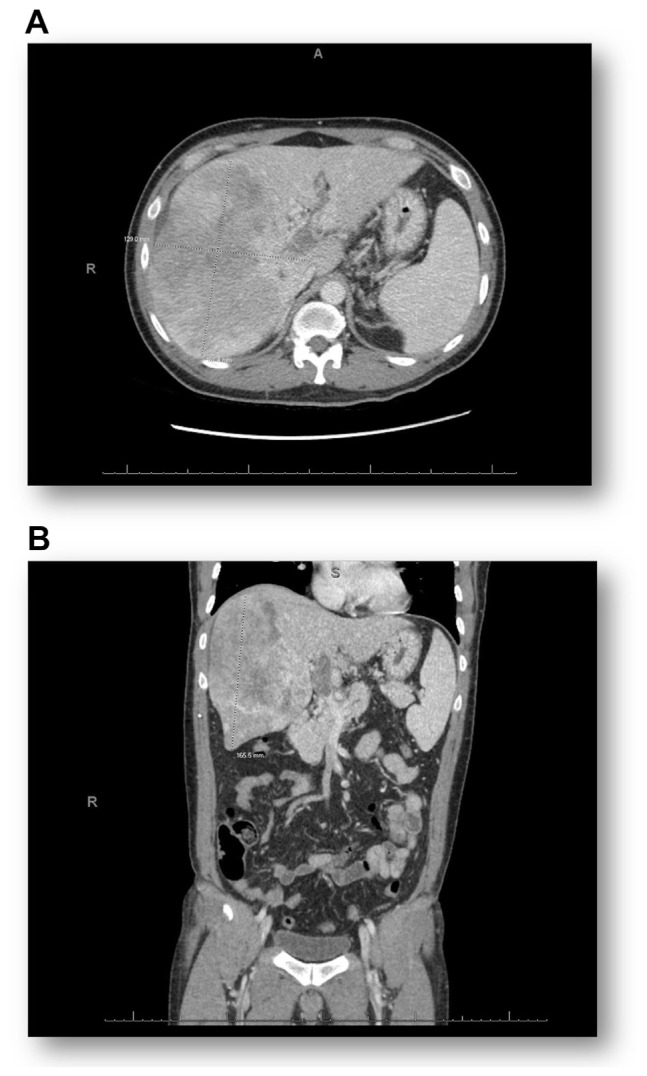

Methods: We present a case of recurrent symptomatic hypoglycemia, despite conservative management, in a patient with extensive hepatocellular carcinoma.